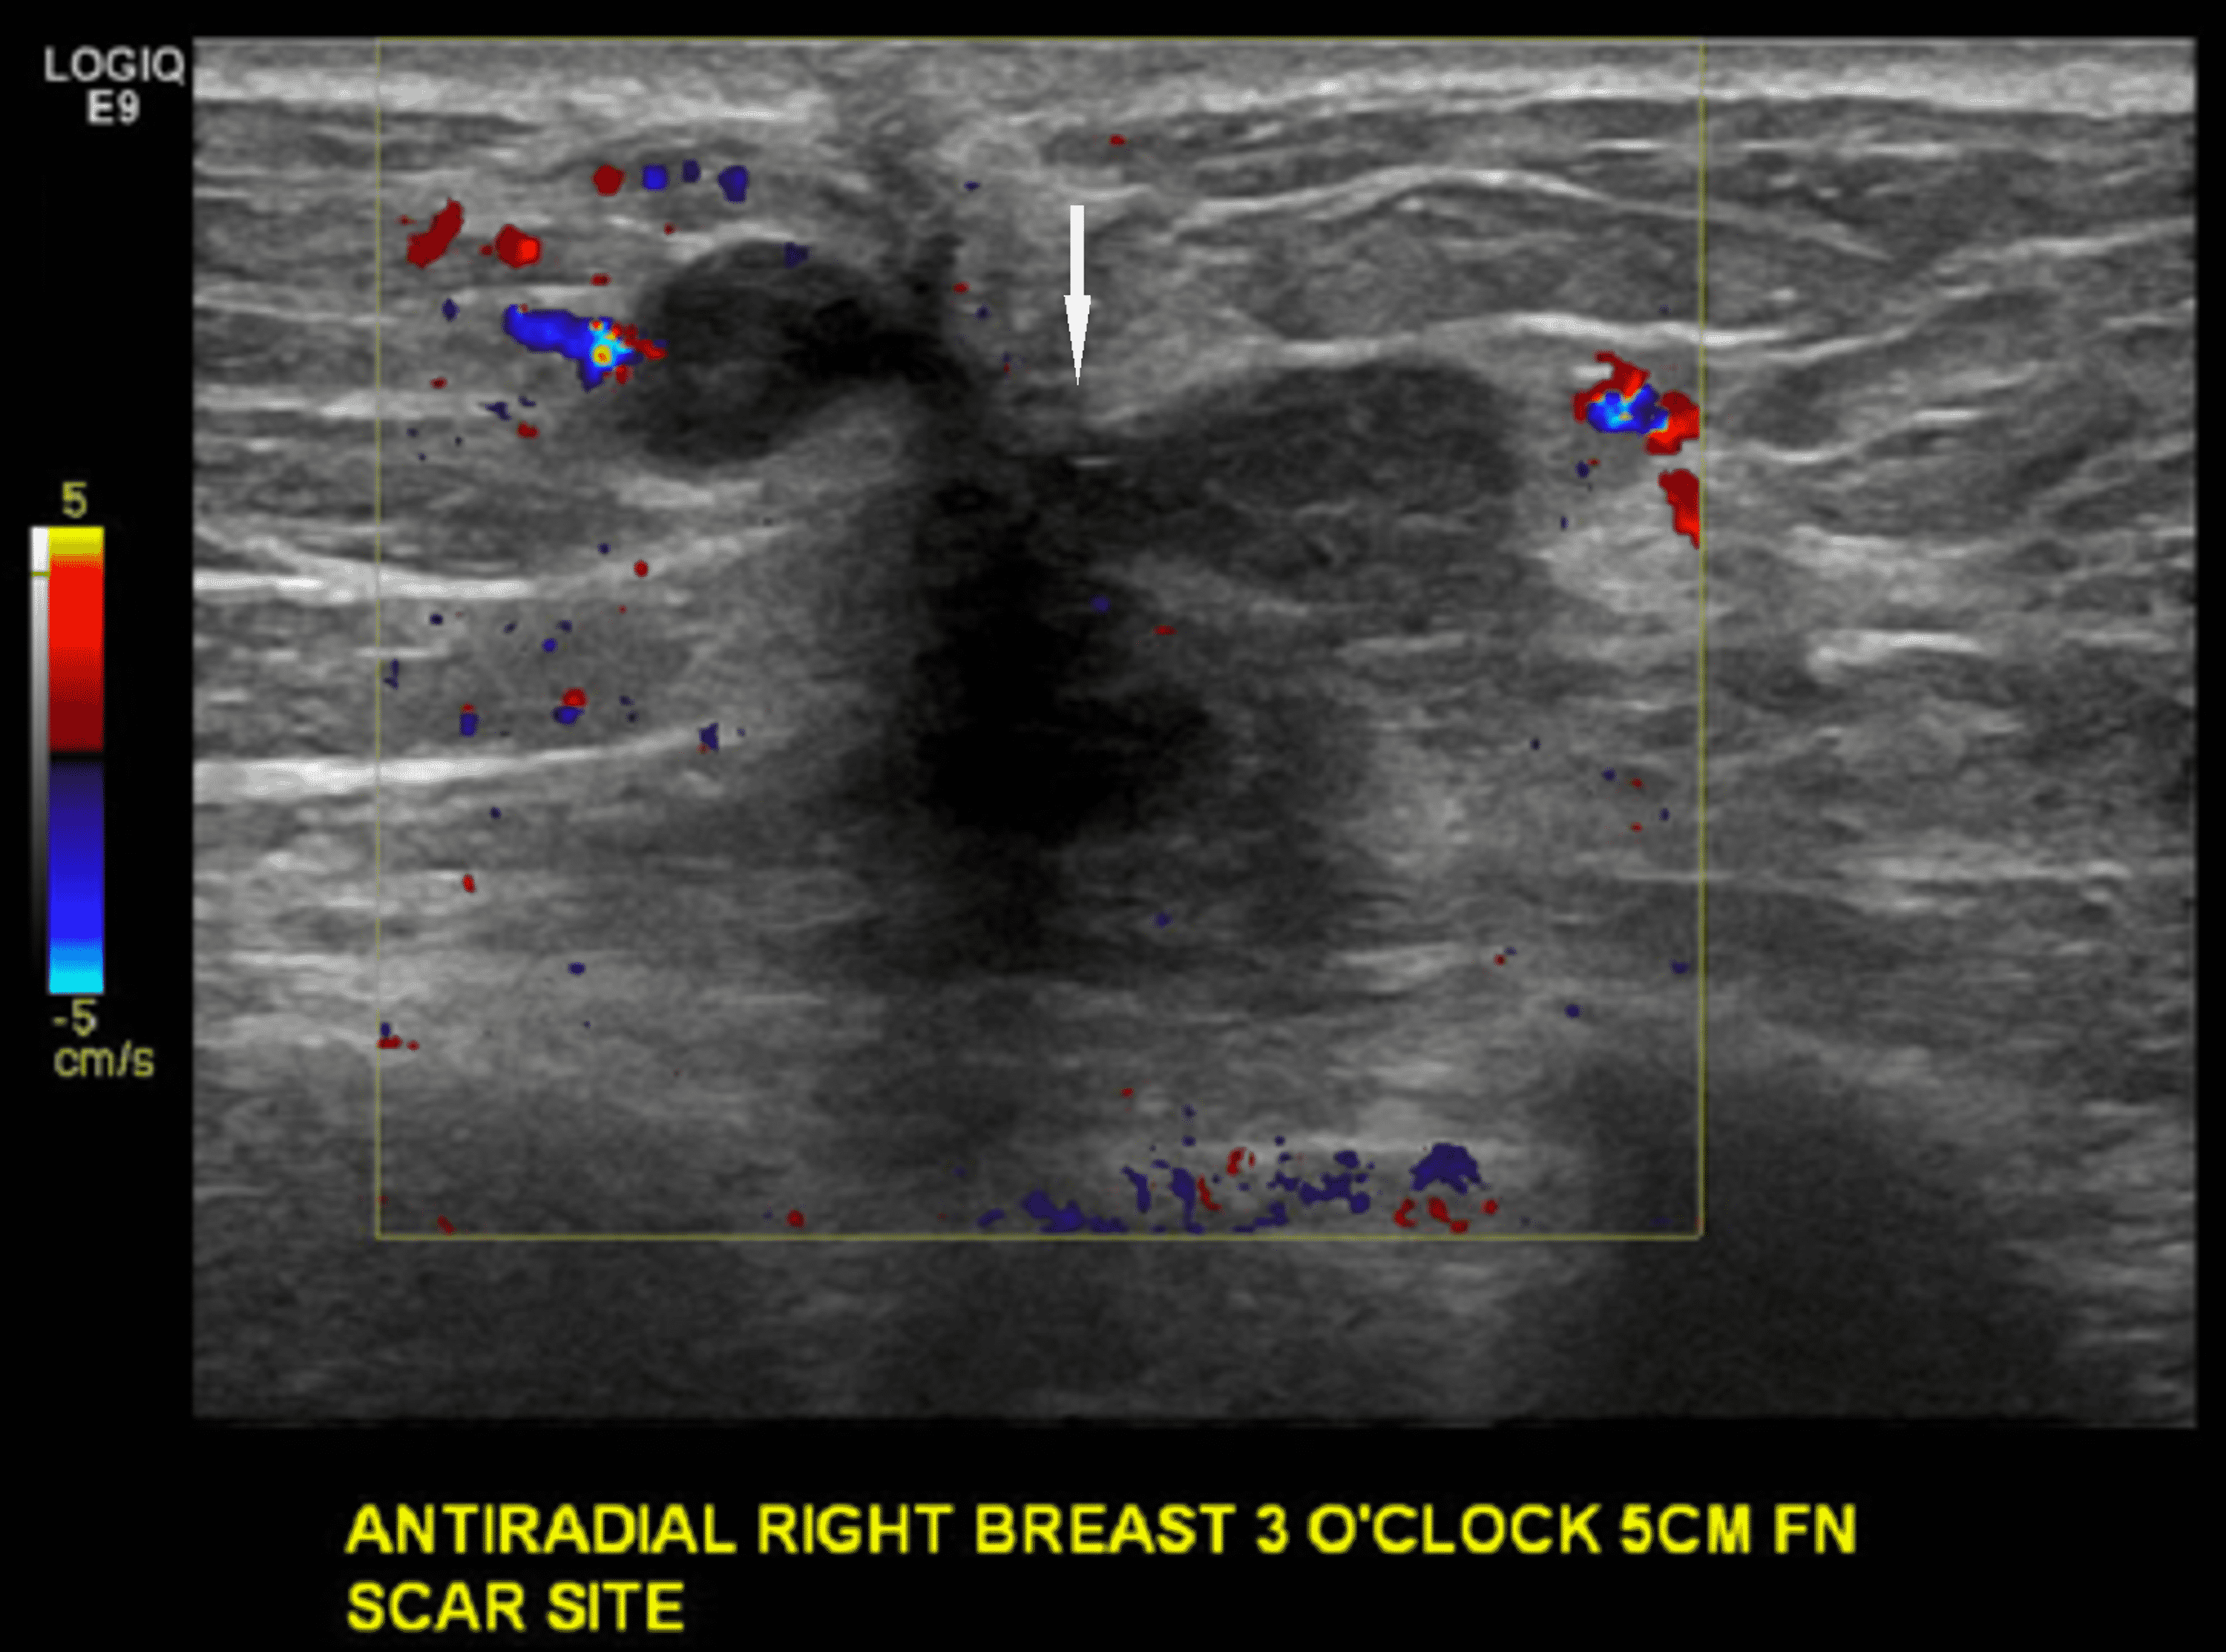

Cureus Invasive Lobular Cancer Arising in a Surgical Scar From Best Cream For Lumpectomy Scar Any moisturiser can be used, as long as it does not contain too much perfume; Following a lumpectomy, tingling and mild pain around the scar are common complaints during the first few days. Your surgeon may have put. Two weeks from now, when your skin is a little less bruised, when your incision is healing even further, now you can. Best Cream For Lumpectomy Scar.